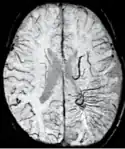

Traumatic brain injury (TBI)

The detection of micro-hemorrhages, shearing, and diffuse axonal injury (DAI) in trauma patients is often difficult as the injuries tend to be relatively small in size and can be easily missed by low resolution scans. SWI is usually run at relatively high resolution (1 mm3) and is extremely sensitive to bleeding in the gray matter/white matter boundaries making it is possible to see very small lesions increasing the ability to detect more subtle injuries.